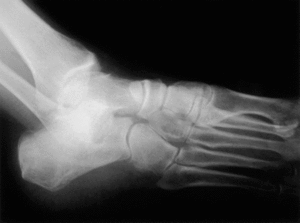

Mujer de 66 años de edad que acude a consulta presentando dolor en el pie derecho de varios meses de evolución. No refería antecedente traumático ni médico de interés. A la exploración física presentaba una tumoración en el borde externo del pie. El estudio de laboratorio mostraba únicamente discreto incremento de la velocidad de sedimentación globular (VSG) (19 mm/h). La radiografía del pie fue normal (fig. 1). En la gammagrafía ósea se apreció incremento de la captación del trazador en el cuboides (fig.2). En la RM había disminución de la intensidad de la señal en T1 e incremento en T2 a nivel de la esponjosa del cuboides acompañado de pequeño edema de partes blandas periféricas (fig. 3).

Figura 3. Imágenes de resonancia magnética (RM) del caso que se describe: (A) RM del pie derecho en T1 que muestra disminución de la señal (hueso negro) al inicio del proceso en cuboides. Se llegó al diagnóstico de osteoporosis transitoria. (B) Misma proyección en T1 al año de evolución. Se observa la normalización de la señal.

Se realizó diagnóstico diferencial con fractura de estrés, metástasis, osteomielitis y necrosis avascular, siendo descartados tras la realización de los estudios con gammagrafía ósea (tecnecio-99 metaestable y galia-67) y RM y analítica. La paciente fue tratada sintomáticamente con antiinflamatorios no esteroideos (AINE) y reposo relativo. Los síntomas cedieron gradualmente en unos 7 meses, con RM normalizada al año del inicio del proceso (fig. 3).